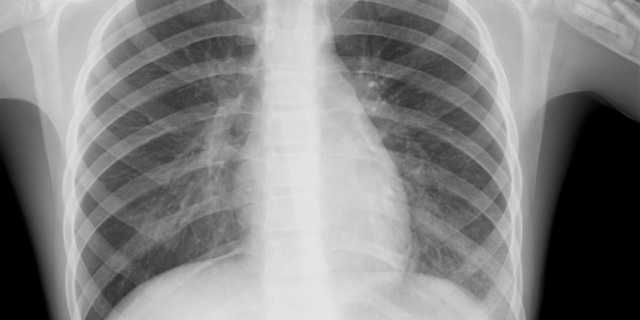

В Николаевской области, где пока не было ни одного случая заражения коронавирусом COVID-19, с начала года зафиксирован аномальный рост пациентов с пневмонией.

Как сообщают "НикВести", главврач Николаевской областной инфекционной больницы Светлана Федорова рассказала, что за январь-март 2020 года в ее больницу с пневмонией попали 56 человек, что в 18 раз больше, чем в аналогичный период 2019 года.

По ее словам, в январе-марте 2018 года в больнице с пневмонией было 2 пациента, а в этот же период 2019 года – только 3 таких больных.

Также Федорова отметила, что если в 2018-2019 годах летальных случаев пневмонии в ее больнице не было, то в этом году зафиксировано уже 2 смертельных случая.